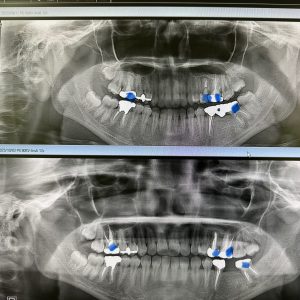

ネチネチ、チマチマ系の根管治療4本

パラタルプレートの再生、ヤグレーザー併用の根管治療のみ

経過みないとね、自然治癒力は素晴らしい!

外科処置の勇み足にならない為の良い症例

最小侵襲で治癒導くが重要

咀嚼に耐え得る歯は保存!